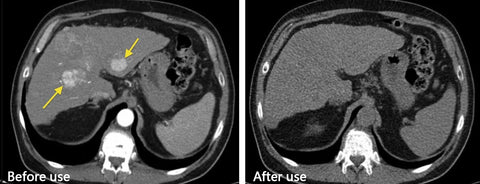

Clinically Proven And Tested By Experts

Prostate health begins with meticulous care! We are proud to present Prostate Herbal Capsules, the highly recommended prostate product by Dr. Roberts, MD.

Clinical studies published in urology journals have provided undeniable scientific evidence of the significant benefits of Prostate Herbal Capsules in relieving prostate discomfort and supporting overall prostate health.